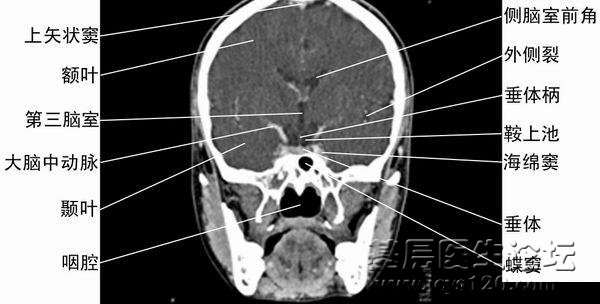

颅脑CT片详解